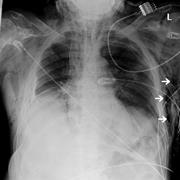

Blunt trauma resulting in pneumothorax with progression to pneumoperitoneum: a unique diagnosis with predicament in management

Karleigh R. Curfman and others

Journal of Surgical Case Reports, Volume 2015, Issue 12, December 2015, rjv147, https://doi.org/10.1093/jscr/rjv147